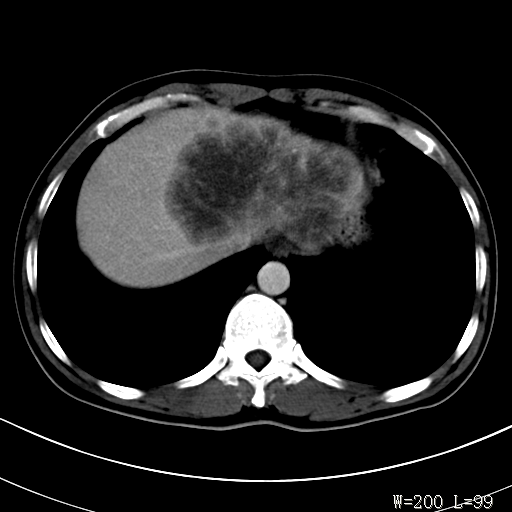

标题: CT27340:肝脏病变?

男,45岁,发热、乏力半月,午后为主。

对比剂快进快出,首先考虑肝左叶巨块型肝癌。

其次,感染性病变,如肝脓疡不排除。

蜂巢,肝脓肿

蜂巢状,支持!肝脓肿的诊断。